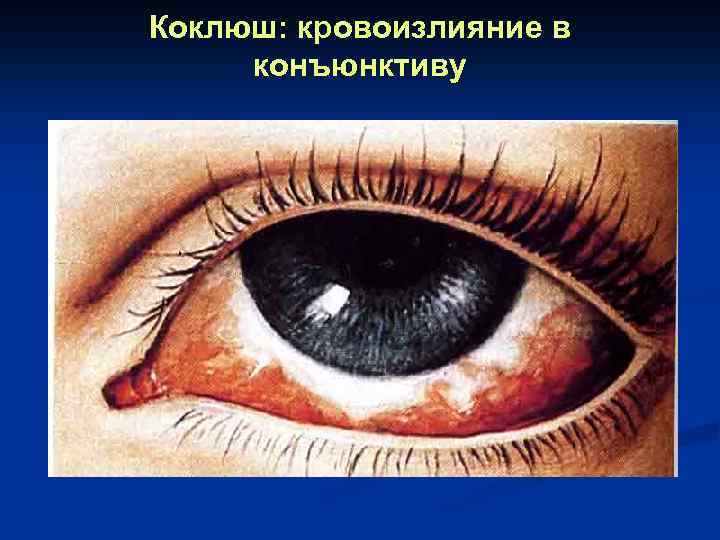

Коклюш: кровоизлияние в конъюнктиву